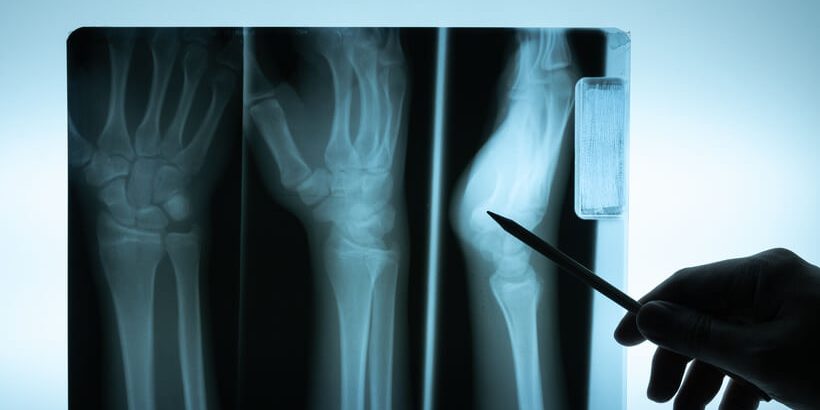

¿Cómo se diagnostica la osteomielitis?

Una vez en el centro el médico se hará un examen físico del paciente preguntándole sobre lesiones recientes en el área donde hay dolor. A su vez, se solicitarán análisis de sangre para saber cuál es la cantidad de glóbulos blancos en la zona afectada (si es alta, habrá infección)Además, detecta, otros signos de inflamación y/o infección. En el caso de que el médico sospeche una osteomielitis, es posible que el médico también recomiende:

- Una resonancia magnética que ofrece una imagen con mayor detalle que las radiografías y permite conocer cuánto tiempo lleva infectado el hueso.